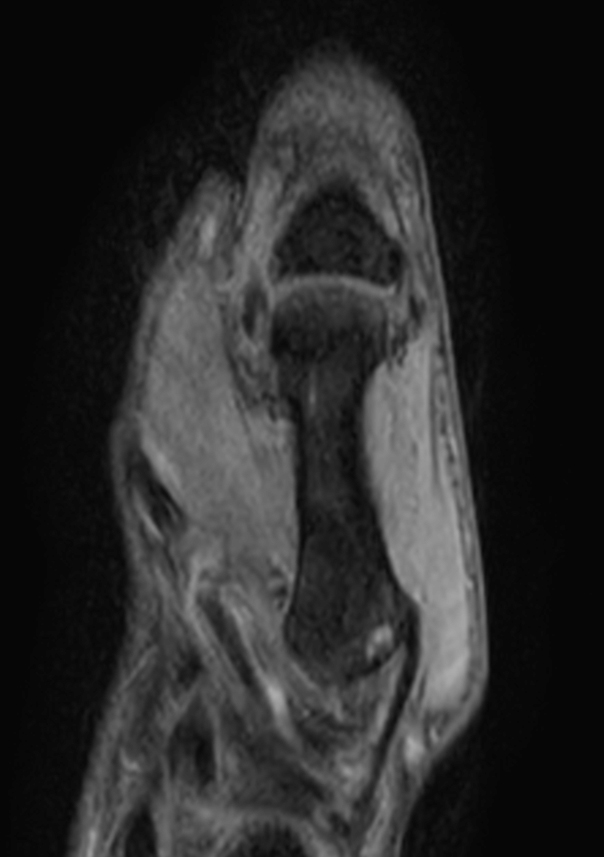

Patient with pathology on the thumb. ExamCard includes mDIXON XD TSE to achieve uniform, complete and consistent fat-free imaging. It simplifies the scan procedure by providing multiple image types in one single scan, including with/without fat suppression contrasts.

Sagittal T1w TSE